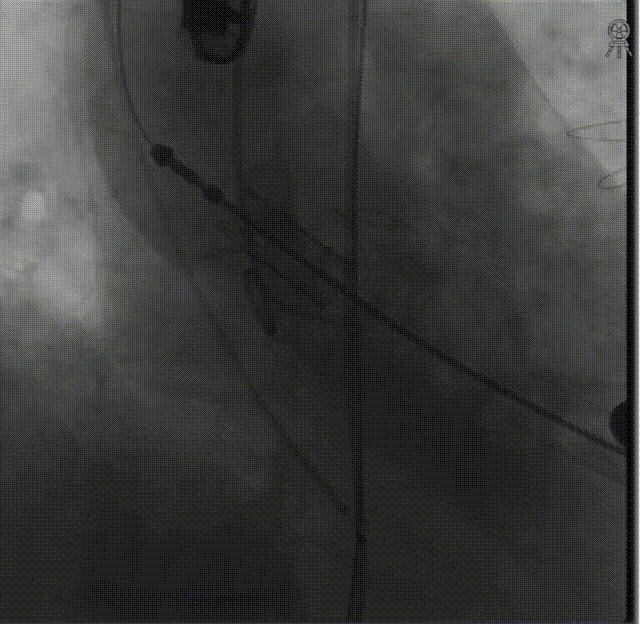

定位件入窦后造影:

降落瓣膜件,完成释放: